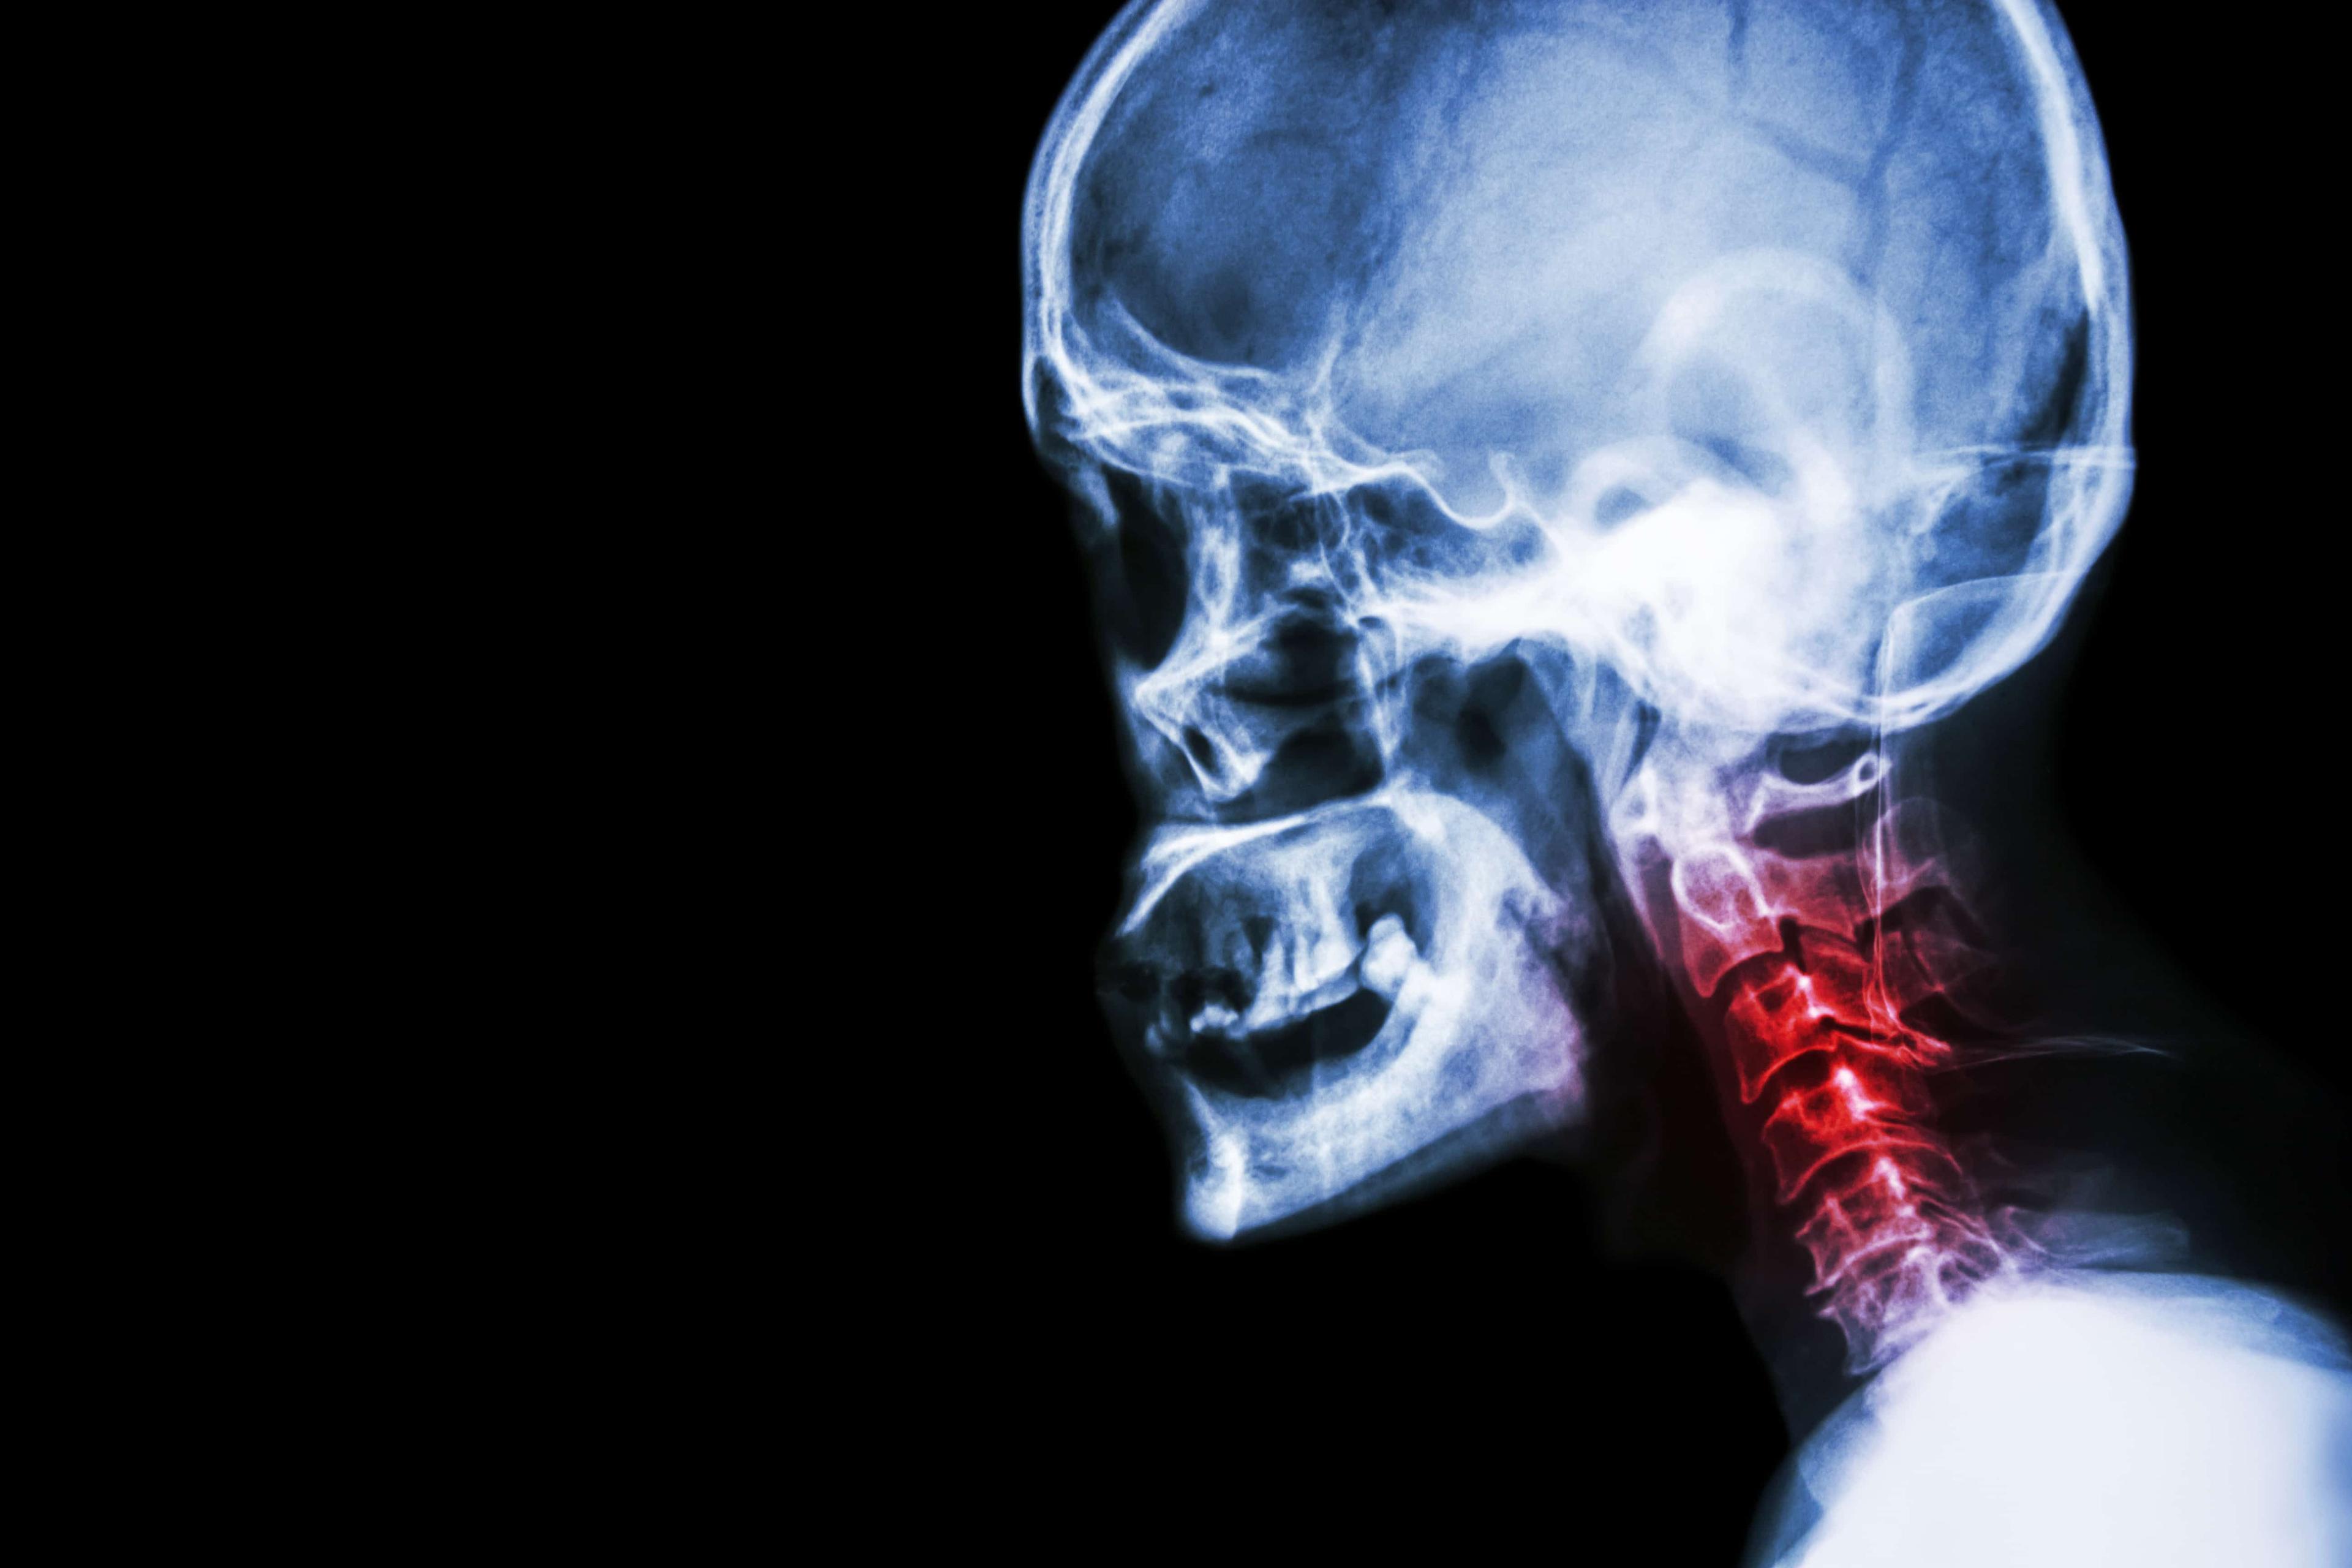

ကိုယ်ခန္ဓာရှိအဆစ်အမြစ်များအတွင်း သွေးယိုတဲ့ အခြေအနေ (Hemarthrosis) ကို ဆိုလိုပါတယ်။ ထိခိုက်ဒဏ်ရာရခြင်းကြောင့် ဖြစ်တတ်သလို ဟေမိုဖီးလျားခေါ် သွေးမတိတ်တဲ့ရောဂါကြောင့်လည်း ဖြစ်တတ်ပါတယ်။ အရိုးအဆစ်များဟာ ကိုယ်ခန္ဓာရဲ့ အစိတ်အပိုင်းတွေ ချောမွေ့စွာ လှုပ်ရှားနိုင်အောင် တည်ဆောက်ထားခြင်း ဖြစ်ပါတယ်။ အကယ်၍ အဆစ်အတွင်းကို သွေးယိုစိမ့်ခဲ့ရင် ရောင်ရမ်းခြင်း၊ နာကျင်ခြင်းတွေဖြစ်တတ်ပါတယ်။ ထိရောက်စွာ မကုသရင် အမြဲတမ်းပျက်စီးသွားနိုင်ပါတယ်။ ဘာလက္ခဏာတွေရှိသလဲ အဆစ်အတွင်း သွေးယိုတဲ့အခါ ဖြစ်နိုင်တဲ့လက္ခဏာတွေကတော့ - အဆစ်များ ရောင်ရမ်းခြင်း - နာကျင်ကိုက်ခဲခြင်း - နီရဲခြင်း - အဆစ်များကို ဖိကြည့်လျှင် လေခိုသလိုဖြစ်နေခြင်း - အဆစ်များတောင့်တင်းခြင်း - သွေးခြည်ဥခြင်း - ပုံမှန်လှုပ်ရှားနိုင်မှုမရှိခြင်း စတာတွေ ဖြစ်ပါတယ်။ ဘာကြောင့်ဖြစ်တတ်သလဲ အဆစ်အတွင်းသွေးယိုခြင်းကို ဖြစ်စေတဲ့ အကြောင်းအရာများကတော့ - ထိခိုက်ဒဏ်ရာရခြင်း၊ အရိုးကျိုးခြင်း၊ အရွတ်များစုတ်ပြဲခြင်း - ခွဲစိတ်ကုသမှုခံယူခြင်း (မှန်ပြောင်းသုံး ခွဲစိတ်ခြင်း အပါအဝင်) - သွေးယိုတတ်သောရောဂါများ (ဥပမာ ဟေမိုဖီးလျား) - သွေးကျဲဆေးများ သောက်သုံးနေခြင်း - ရောဂါပိုးဝင်ခြင်း - […]